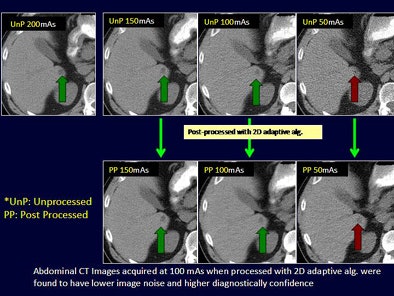

- Abdomen mAs settings: 200, 150, 100, 50

Regardless of radiation dose, postprocessing with image filters improved subjective noise for both chest and abdominal CT and helped lower CT radiation dose levels for the chest by up to 40 mAs and for the abdominal CT by up to 100 mAs, Singh said.

The quantitative average image noise in postprocessed low-dose chest and abdominal CT images was significantly lower than in low-dose unprocessed images (p < 0.001).

Although the diagnostic confidence of low-dose postprocessed images was high at 40 mAs for chest CT, postprocessed abdominal CT images were rated as "fully confident" only at 100 mAs and not 50 mAs, the group reported.

Adaptive filtering decreases image noise and enhances the diagnostic confidence of low-dose chest (40 mAs) and abdominal (100 mAs) CT exams, they concluded.